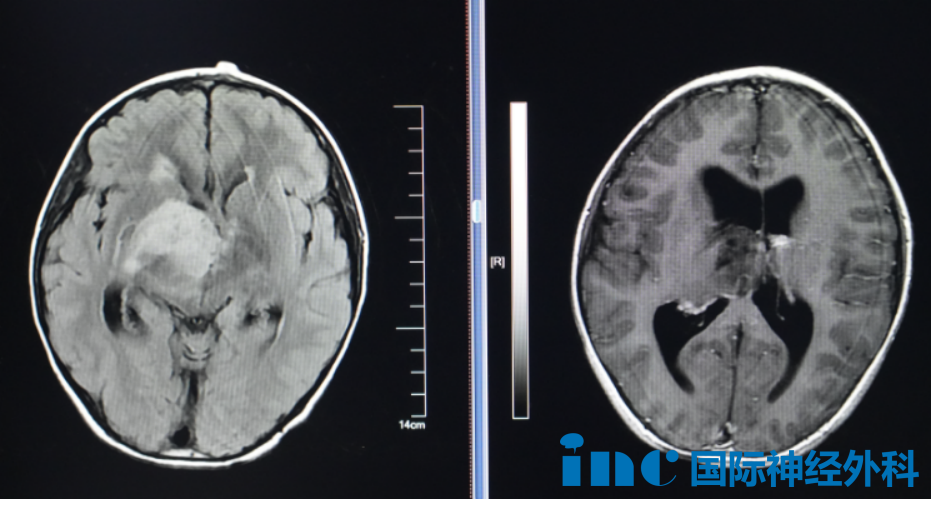

它悄然潜入8岁小航的大脑,盘踞在右侧丘脑与基底节区。初次发现时,肿瘤已显露出不容小觑的规模——病灶大小约4.0cm×4.7cm×4.8cm,高度怀疑为弥漫中线胶质瘤,并引发了梗阻性脑积水。在这幼小的头颅中,肿瘤开始悄然作恶:小航出现记忆力减退、注意力难以集中,甚至喝水时呛咳。

巴教授在详细评估后,给出了明确而坚定的判断:孩子有明确手术指征,应尽快手术,不能再拖延。而对于这个胶质瘤,巴教授表示可能是低级别胶质瘤,但还是要看最终手术病理。“